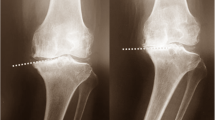

All radiographs were digitally acquired using a picture archiving and communication system viewer (INFINITT PiviewSTAR; Infinitt Healthcare, Seoul, Korea). The lower extremity alignment was determined using the mechanical tibiofemoral angle (mTFA). This angle was defined as the angle formed between the mechanical axis of the tibia and that of the femur (Fig. 2). The mechanical axis of the femur was defined as the line connecting the center of the femoral head and the center of the femoral notch. The mechanical axis of the tibia was defined as the line connecting the point between the medial and lateral tibial spines and the center of the tibial plafond. The mTFA was assigned a negative value when the knee was in varus alignment. The participants were divided into three groups according to the preoperative mTFA varus deformity as follows: neutral (0°) to 5°, between 5° and 10°, and more than 10° of varus deformity [38].